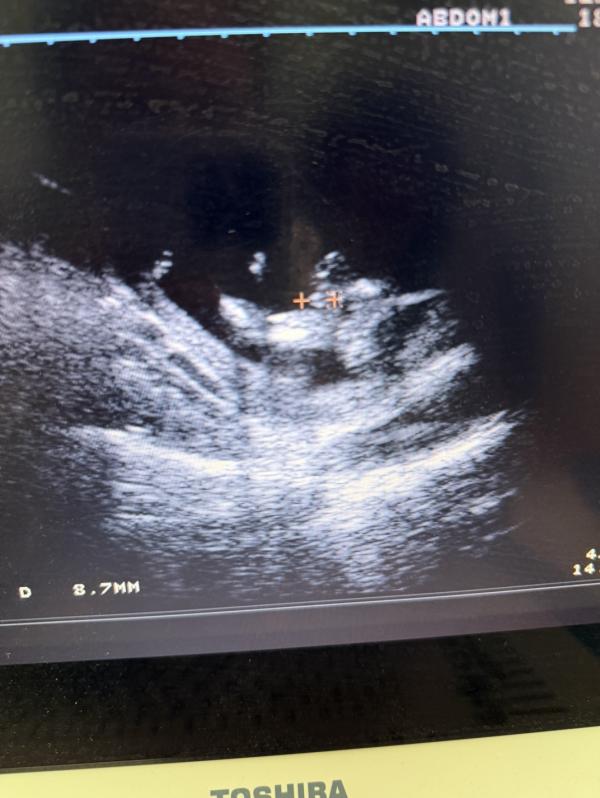

Девочка как думаете мальчик или девочка?

Срок какой ? На писюн похоже

16 недель

@melaniya.sementsova, тогда мальчик